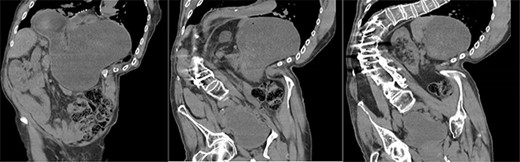

A 67-year-old man presented to the emergency department with sudden onset epigastric abdominal pain and vomiting, on a background of a known hiatus hernia awaiting surgical management. The patient continued passing flatus but was not able to tolerate any per oral fluid intake, vomiting any intake that was attempted. Medical history was relevant for severe KS, spina bifida, reflux, recurrent urinary tract infection, and an anterior approach spinal fusion surgery. Examination was significant for severe KS, with a soft and non-tender abdominal examination. Biochemically, the patient had a very mildly raised white cell count of 12.6 † 109/l. A CT of the abdomen and pelvis was obtained that identified the progression of a known hiatus hernia in comparison with an earlier CT, containing the distal portion of the stomach. The CT showed a distended and fluid filled oesophagus and stomach, along with fat stranding around the distal stomach, concerning for obstruction and possible strangulation of the moderate hiatus hernia, along with the known severe KS (see Figs 1 and 2). A nasogastric tube was placed to decompress the stomach (see Fig. 3). Following discussion with the patient regarding their current presentation and risks of operative management, laparoscopic hiatus hernia repair and fundoplication was undertaken, which was uncomplicated, although the dissection was difficult secondary to the severe scoliosis. Intra-operatively, it was noted that the hernial sac contained a grossly dilated stomach, with all hernial contents assessed as being viable, with nil signs of ischaemia. The peritoneal sac was not resected and left in situ, with a four-stitch horizontal posterior cruroplasty undertaken, along with a 180-degree anterior fundoplication. There was concern that recovery may be complicated by respiratory failure due to the severe KS; however, the patient had no respiratory compromise, begun passing flatus, opened his bowels, and tolerated a puree diet in the days following the operation. At post-operative clinic review 4 months following the hiatus hernia repair, the patient was well, described nil issues, and was tolerating a full diet.

Axial slices of CT scan showing a moderate hiatus hernia with concern for obstruction and strangulation, with severe kyphoscoliosis.